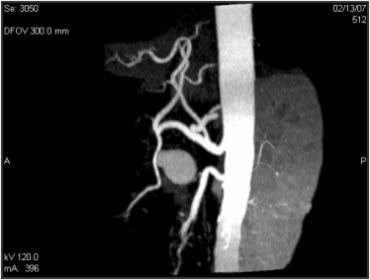

Mesenteric Artery Aneurysm

Hepatic Aneurysm Coiling